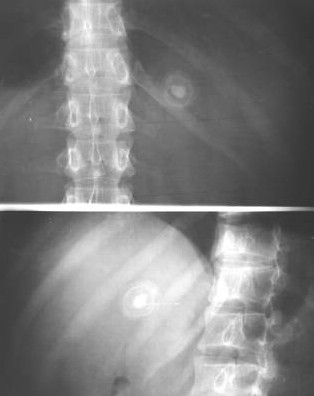

照片名称:胸椎压缩性骨折